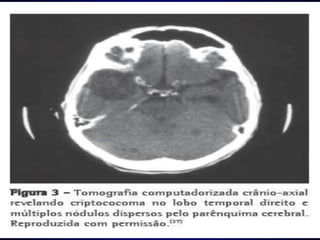

CRIPTOCOCOSE    A Criptococose também conhecida por Torulose, BlastomicoseEuropeia ou Doença de Busse-Buschke é uma doença, micose causada pelo fungoCryptococcusneoformans. As manifestações mais comuns são a pneumonia e a meningite, sendo esta última de particular importância. Juntamente com a candidíase, a criptococose, são infecções fúngicas oportunistas no portador de HIV.Eliene

CRIPTOCOCOSEOs criptococos crescem no ser humano em formas unicelulares, leveduras encapsuladas com 5 micrómetros, de replicação assexuada por geminação.Existe em todo o mundo. Haverá um caso de meningite em um milhão de pessoas por ano. A infecção é pela inalação de esporos, frequentemente em detritos de pombos.Eliene

CRIPTOCOCOSEApós inalação, as leveduras multiplicam-se no pulmão, frequentemente de forma assintomática. Mais tarde disseminam-se pelo sangue, especialmente para o cérebro. Sintomas são aqueles de todas as meningites mas de intensidade mais moderada: dor de cabeça, náuseas, vómitos e fotofobia (sensibilidade exagerada à luz), que podem durar várias semanas (ao contrário da meningite bacteriana que é fatal em apenas algumas horas).Eliene

CRIPTOCOCOSEA sorologia, com detecção de anticorpos específicos contra o fungo é usada também.O tratamento é com o fármaco antifúngicoanfotericina B, ou com derivados de azol, como itraconazol.Eliene